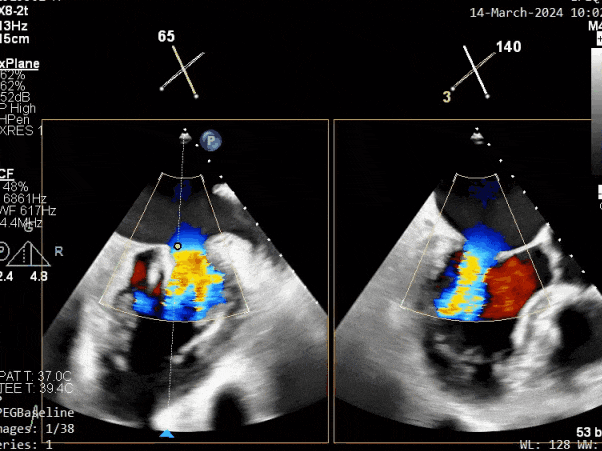

二尖瓣后叶活动受限,呈房源性栓系,以P3区为重,二尖瓣前叶假性脱垂,二尖瓣瓣环前后径49mm,左右径40mm。

二尖瓣反流(重度,4+级,Carpentier I型)

释放瓣膜夹后评估,二尖瓣呈双孔,外侧仍有残余反流

第二个瓣膜夹释放后评估,二尖瓣呈双孔,外侧仍有残余反流

第三个瓣膜夹释放后评估,释放后评估,二尖瓣呈双孔,组织桥张力合适,瓣膜夹轴向与二尖瓣闭合线垂直,无残余反流

2. 本例患者外院超声心动图考虑二尖瓣前叶脱垂,入院后经食道超声心动图明确该患者为二尖瓣后叶活动受限,呈房源性栓系,二尖瓣前叶假性脱垂,超声特征表现为心房功能性二尖瓣反流终末期,呈现出很典型的二尖瓣后瓣环向左室游离壁顶部位移和后叶挛缩表现,同时合并有明显的二尖瓣瓣环扩张、圆形化,左房增大等不利因素,术中通过精准的影像指导和手术操作,成功行TEER,二尖瓣反流程度减轻至微量。